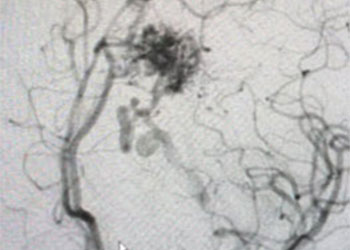

Endovascular:

CME:

Direct Carotid Cavernous Fistula (CCF)

Author: Jonathan L. Brisman M.D., F.A.C.S., Read More!